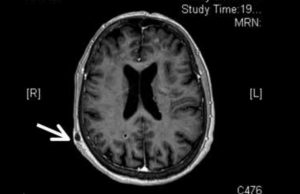

Baisse d’acuité visuelle, fièvre et asthénie : comment traiter cette patiente ?

Mme V., 77 ans, a été adressée dans notre service pour une exploration d’une baisse d’acuité visuelle de l’oeil gauche, associée à un fébricule et une asthénie évoluant depuis 15…